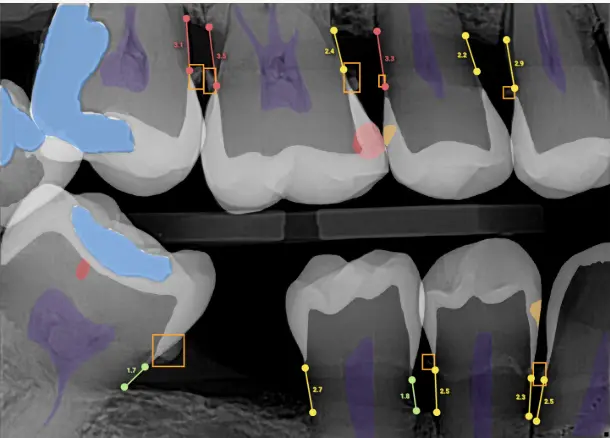

AI-assisted radiographic analysis can detect subtle radiolucencies that may be difficult to identify in their earliest stages. Research suggests that machine learning models can increase sensitivity for early caries detection, particularly in interproximal areas.

Bone level measurement is critical in diagnosing and staging periodontal disease. AI software can quantify bone loss on radiographs and provide standardized measurements. This reduces variability and improves documentation over time.

One of the most practical advantages of AI is visual communication. Many platforms overlay color-coded markers on radiographs, helping patients see areas of concern clearly.